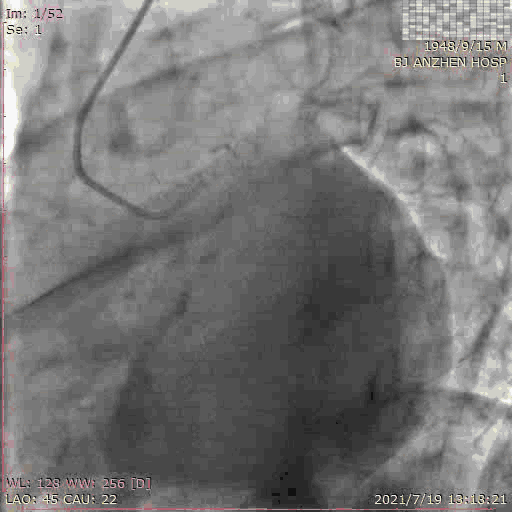

PCI过程:术中使用 7F AL 0.75 Guiding,顺利于RCA植入2.5*18mm支架,术后予双联抗血小板治疗,恢复良好。